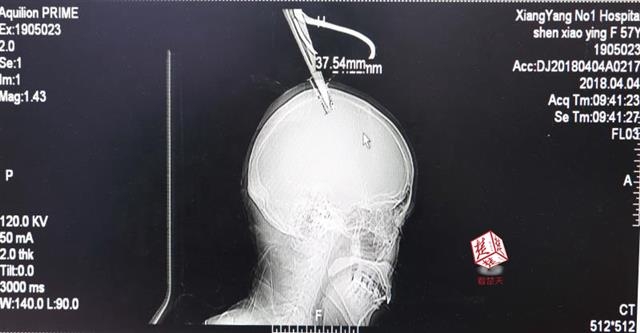

女子顱骨插進剪刀 不慌不忙坐公交車就醫

醫生檢查發現,剪刀刀尖斜嵌在沈某顱骨里,離腦髓只有兩三毫米。所幸是斜著插進去,如果是垂直刺入,很有可能造成癱瘓。

4月4日清晨,襄陽市樊城區太平店鎮57歲的農村婦女沈某,在采摘香椿嫩芽時,綁在竹桿上的剪刀因竹子腐朽不慎折斷,剪刀斜插入頭顱。經過及時搶救,目前脫離生命危險。

“當時感覺還好,就是頭有點木。”沈某說,由于自己感覺沒什么大礙,便沒坐120急救車,而是和家人一起坐了一個小時的公交車趕到市區醫院。

醫生檢查發現,剪刀刀尖斜嵌在沈某顱骨里,離腦髓只有兩三毫米。所幸是斜著插進去,如果是垂直刺入,很有可能造成癱瘓。最終經過手術,剪刀被取出,沈某目前仍在ICU進一步觀察。